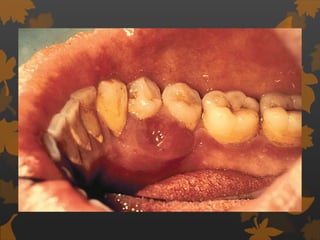

Effect on gingiva

 Tendency towards enlarged gingiva,

sessile/ pedunculated gingival polyp,

polypoid gingival proliferation, abcess,

periodontitis , mobility of teeth.

Hirschfeld I, 1934

PERIODONTAL MANIFESTATIONS

 Tendency towards enlarged gingiva.

 Sessile/pedunculated gingival polyps.

 Polypoid gingival proliferations

 Abscess formation

 Periodontitis

 Loosened teeth - Hirchfeld I (1934)